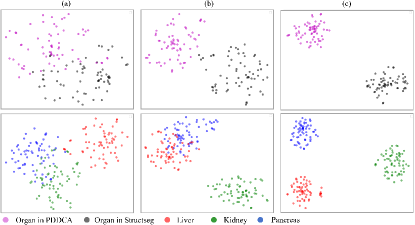

Feature Visualization. To verify that the difference learning can make the features of different organs extracted by different models more distinguishable, we used t-SNE to visualize the high-dimensional features extracted by different models on the same dataset. As shown in Fig. 9, without difference learning (Fig. 9 (a)), the features of different organs significantly overlap, which reduces the segmentation performance of the model and the quality of the pseudo labels. Introducing PD loss (Fig. 9 (b)) provides some distinguishability among the features of different organs, but overlap still persists. After adding FD loss (Fig. 9 (c)), the features of different organs are clearly separated, leading to higher precision in segmenting different organs by different models, and also improving the quality of pseudo labels generated on other datasets, significantly reducing the occurrence of overlap with labels from other organs.